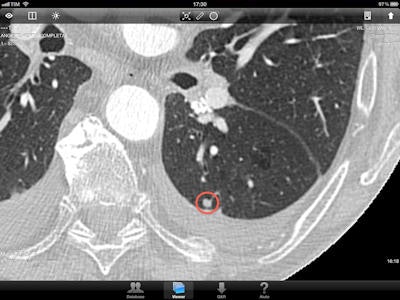

Screen capture of a pulmonary nodule as displayed on the iPad 2. All images courtesy of Dr. Lorenzo Faggioni.

Screen capture of a pulmonary nodule as displayed on the iPad 2. All images courtesy of Dr. Lorenzo Faggioni.There is still some resistance to the use of mobile devices in clinical practice, due to the fear that these devices may perform less optimally than regular workstations, thus bringing the risk of missing lesions or making wrong diagnoses. However, Faggioni said the screen resolution of the iPad 2 is more than adequate for 2D analysis of CT and MRI examinations, where pixel matrices are relatively low -- typically 512 x 512 for CT and often less for MRI. First impressions of using the iPad 2 for the visualization of small lesions is that the image quality of CT and MRI studies on the iPad 2 is comparable with that perceived on conventional workstations, the researchers found.